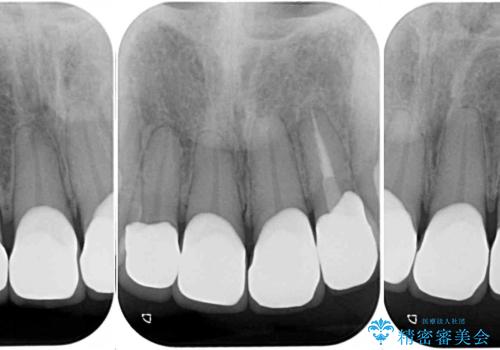

- 前歯の虫歯や治療跡が気になるとのことで来院された患者様です。

以前矯正治療をされ、その時には歯列が整ったので満足されたそうですが、若干の後戻りにより隙間ができ、矯正治療前に治療していた虫歯の跡が気になったため、オールセラミックによる審美治療を希望されました。

目立つ範囲である前歯4歯をオールセラミッククラウンにて補綴することとしました。